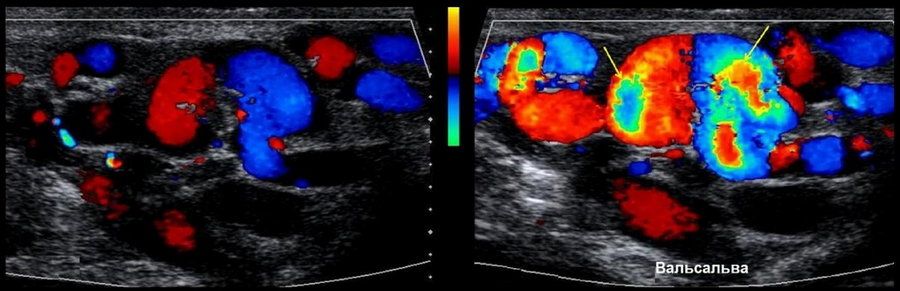

Когда проводится проба вальсальвы при варикоцеле, пациенту предлагают выдохнуть воздух и удерживать дыхание, после чего пациент напрягается, подобно попытке выдохнуть при закрытом рту и носу. Это приводит к увеличению внутрибрюшного давления.

- Положительный — если при проведении обнаруживается увеличение размера варикоцеле или ухудшение кровотока в венах мошонки, это может указывать на более серьезное состояние.

- Отрицательный — отсутствие изменений в размере или кровотоке во время пробы Вальсальвы может свидетельствовать о менее выраженном варикоцеле.